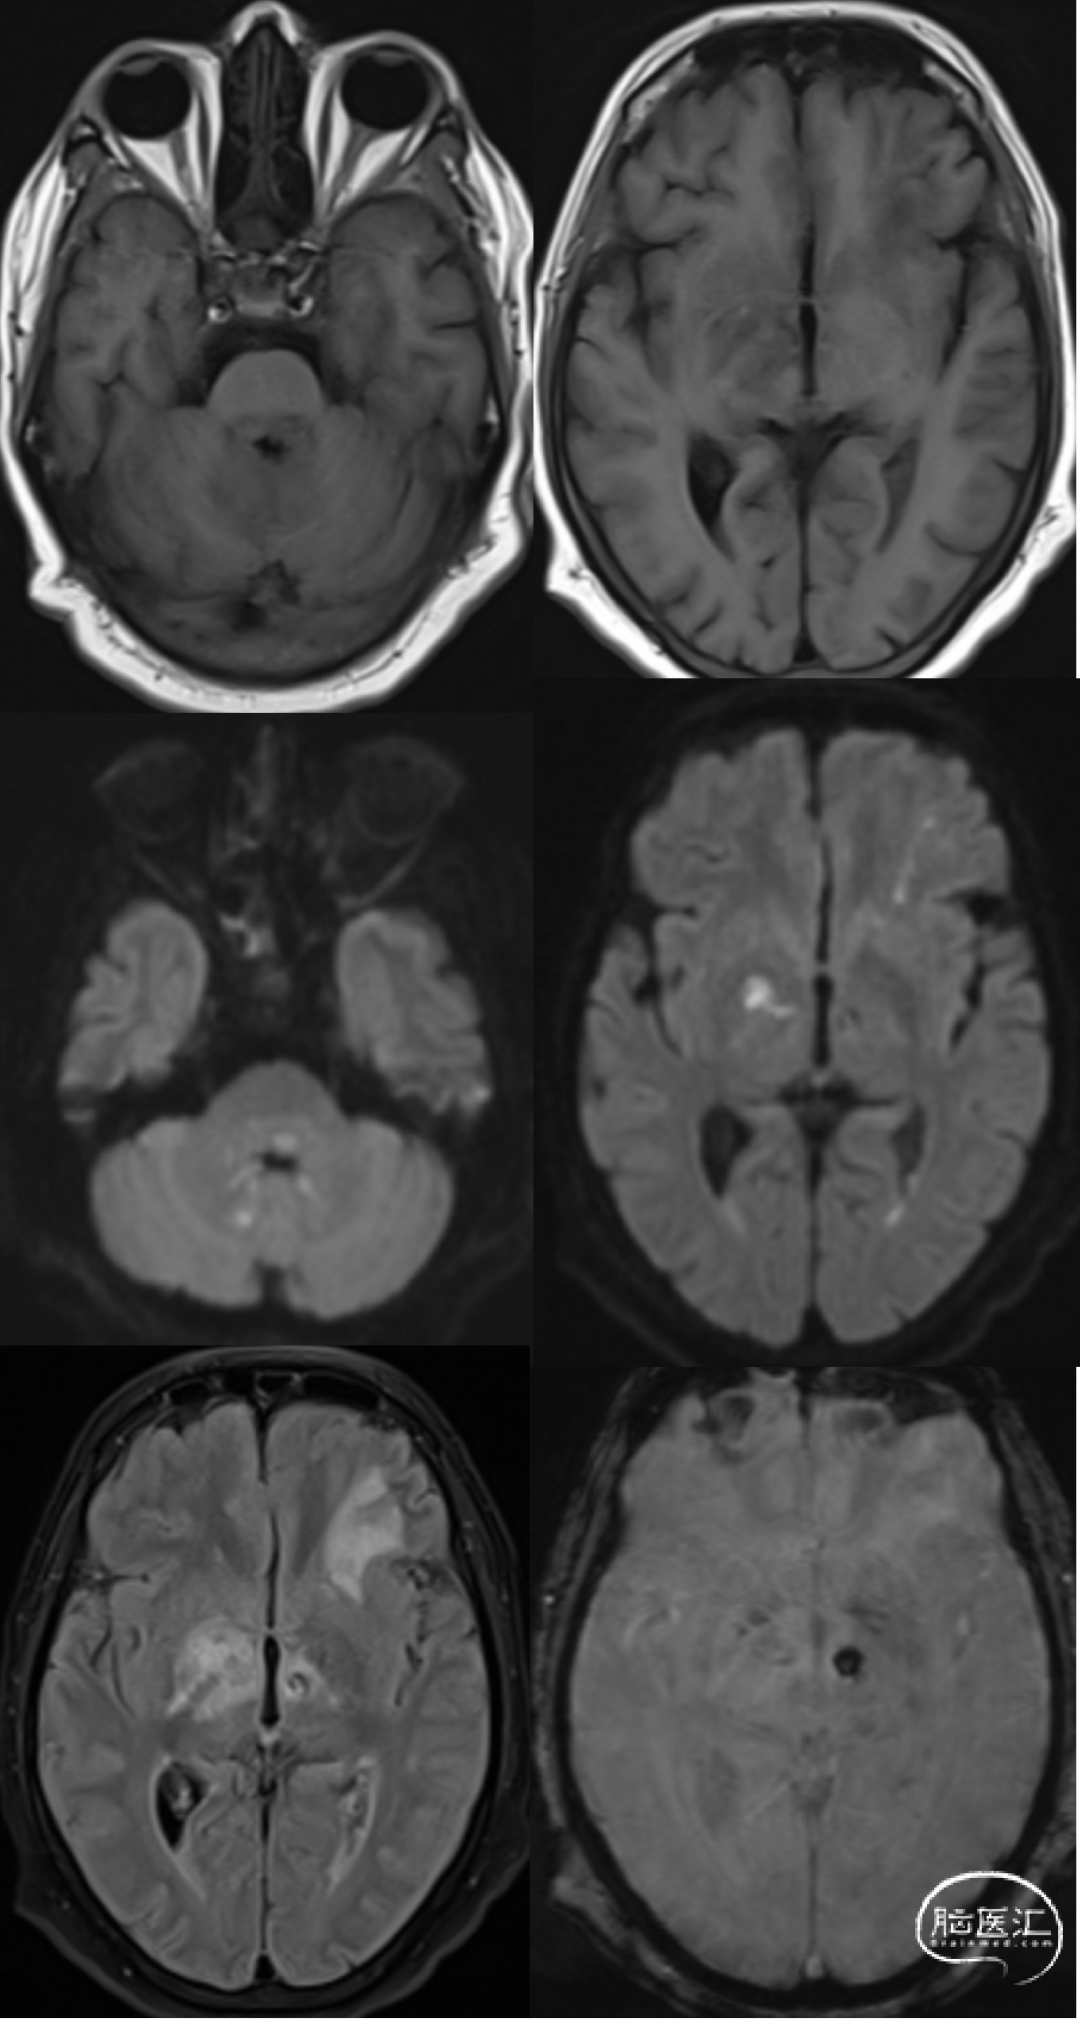

男,55岁,发热15天,精神异常2天。

李斯特菌是一种厌氧菌,被认为是菱形脑炎最常见的病因,通常见于老年人。它的死亡率高(~50%),幸存者经常出现严重后遗症(~60%)。

菱形脑炎是指影响后脑(脑干和小脑)的炎症性疾病,病因多种多样,包括感染、自身免疫性疾病和副肿瘤综合征,单核细胞增生李斯特菌被认为是最常见的病因。菱形脑炎的发病率和死亡率很高。